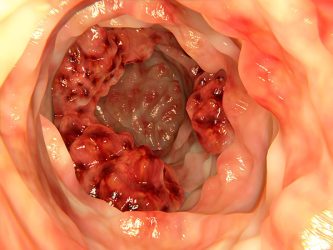

Mε τον όρο καρκίνος παχέος εντέρου εννοούμε το κακόηθες, εκείνο νεόπλασμα, το οποίο αναπτύσσεται στο παχύ έντερο ή στο ορθό. Ο καρκίνος του παχέος εντέρου είναι ένας από τους συχνότερους καρκίνους στον κόσμο.

Πολλοί συγχέουν τον καρκίνο του παχέος εντέρου με τους πολύποδες, οι οποίοι είναι περιγεγραμμένα μορφώματα διαστάσεων από λίγα χιλιοστά έως μερικά εκατοστά και προβάλλουν με ή χωρίς μίσχο στον αυλό του εντέρου. Αποτελούν συχνό πρόβλημα κα μπορεί να εξαλλαγούν σε αδενοκαρκίνωμα ή να συνυπάρχουν με αυτό.

Πολλές φορές ο καρκίνος του παχέος εντέρου μπορεί να είναι ασυμπτωματικός ή να εκδηλώνεται με κάποιο από τα παρακάτω συμπτώματα :

• Αναιμία

• Αίμα στα κόπρανα

• Αλλαγή στις συνήθειες αφόδευσης -εμμένουσα διάρροια ή δυσκοιλιότητα.

• Απώλεια βάρους

• Αίσθημα ατελούς αφόδευσης

• Βύθιο κοιλιακό άλγος

Επίσης ο καρκίνος μπορεί να προκαλέσει  απόφραξη του εντέρου.  Τα συμπτώματα τότε γίνονται έντονα: εμετός,  δυσκοιλιότητα, επίμονος πόνος και διάταση (φούσκωμα) της κοιλιάς.